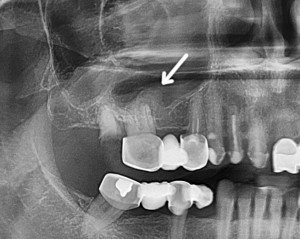

Клиническая картина. Периодические гнойные выделения из носового хода, часто со зловонным запахом, возможные обострения с появлением болей в области пазухи, ее затемнение на рентгенограмме, нарушение носового дыхания, парестезии и боли в области разветвлений верхнечелюстного нерва.

Наличие в области лунки удаленного зуба свищевого хода, ведущего в пазуху — достаточное свидетельство хронического гайморита, возникшего в связи с перфорацией дна пазухи. Дифференциальный диагноз следует проводить с околокорневой кистой, опухолью верхней челюсти.